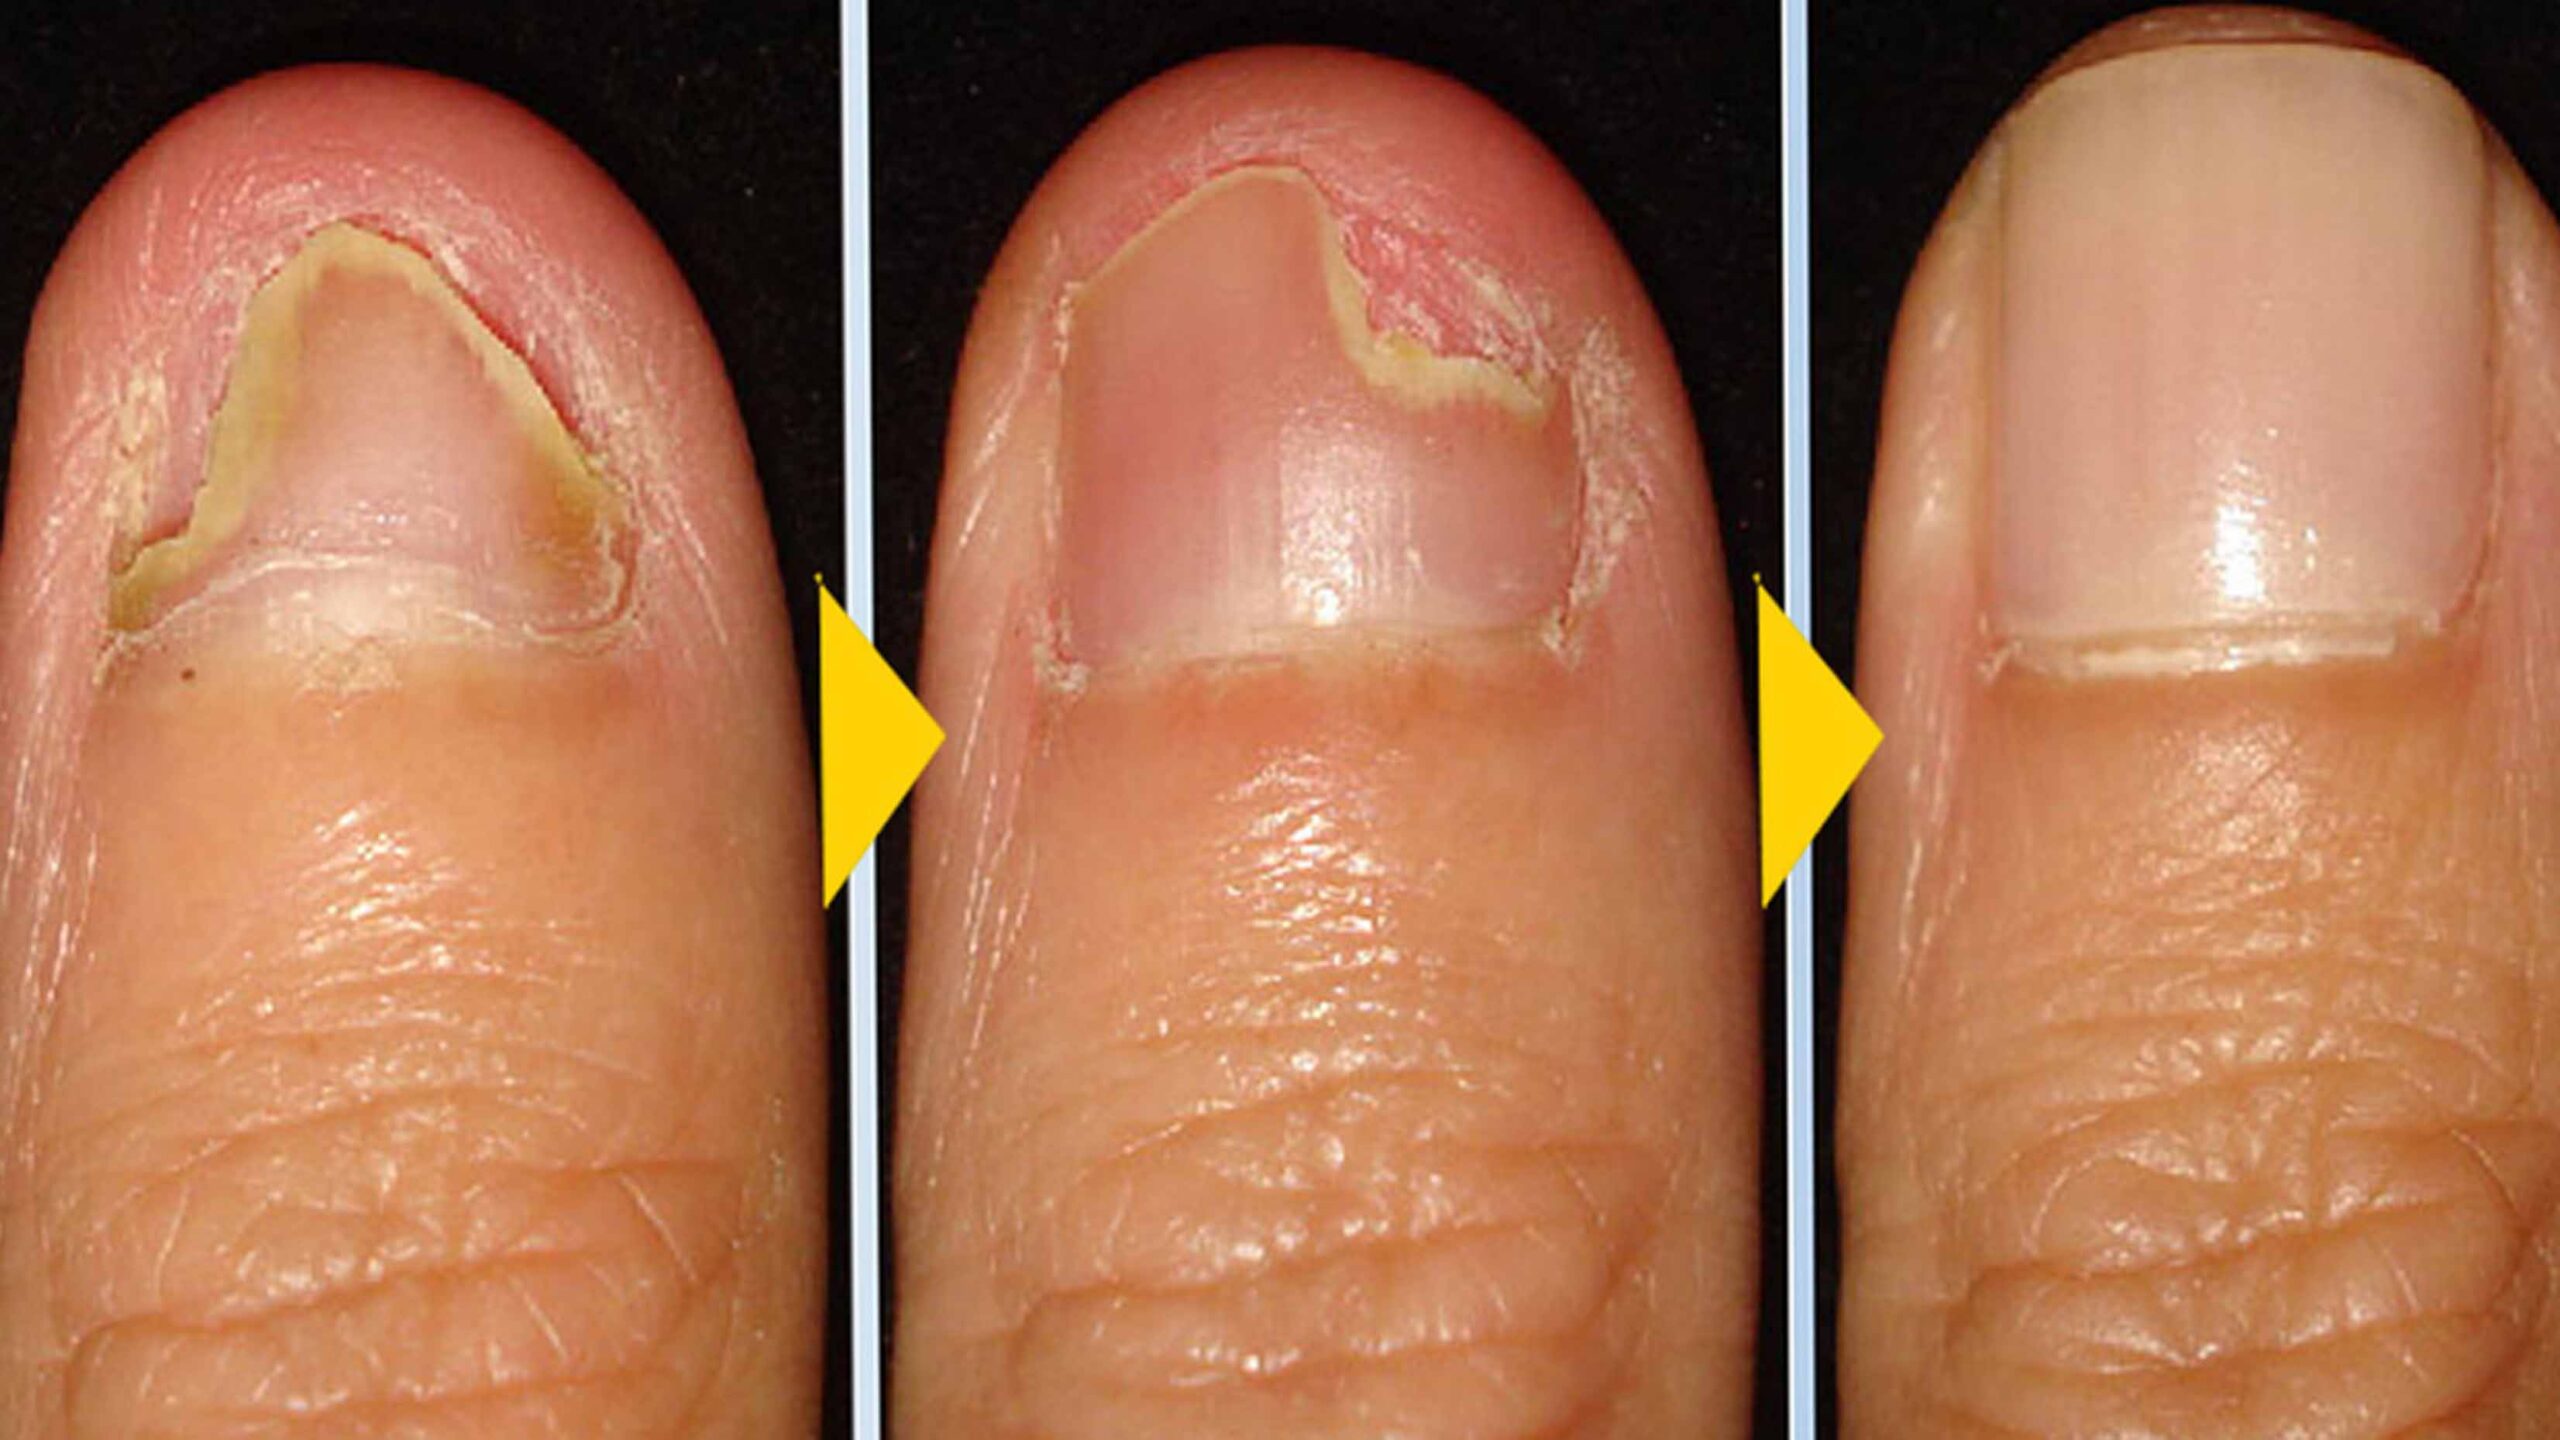

Let us squash any doubts you may be having right now — the Swissklip Klearnail Anti-Fungal Stick really does work and it was the most efficient treatment among all the options tested.

After starting the test, some patients noticed noticeable improvements in as short as one week – the burning and itching were significantly better in just 7 days.

In 30 days, virtually every patient saw their fungus get completely eliminated. The ingredients in Swissklip’s Anti-Fungal treatment killed fungus on contact, preventing the spread of fungus to other parts of the body.

It even treated less-than-desirable nail thickness and some patients related seeing their toenails getting shiner.

In short, the results left everyone speechless. So, we could confirm it as our Top Choice and highly recommend this product to anyone who wants to say goodbye to toenail fungus forever!